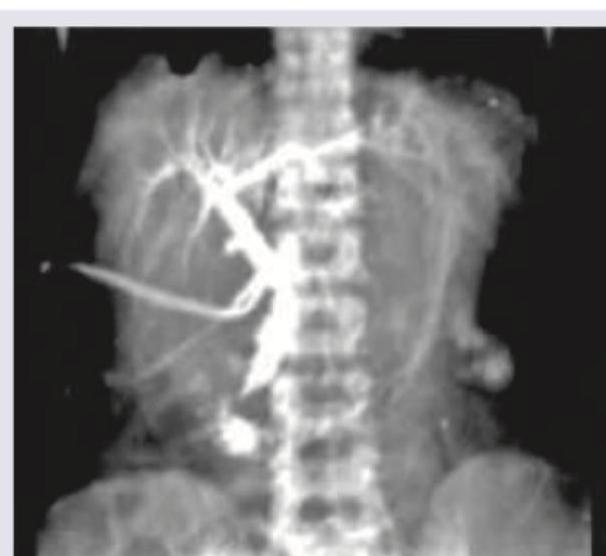

The following image shows: (DNB Pattern 2018)

Explanation: ***Postoperative T- Tube cholangiogram*** - This image clearly shows a **T-tube** in place, which is typically inserted into the **common bile duct** during surgery to allow for drainage and subsequent imaging of the biliary tree. - The contrast material delineates the bile ducts, consistent with a **postoperative cholangiogram** performed via the T-tube to check for patency and stones. *ERCP* - **ERCP (Endoscopic Retrograde Cholangiopancreatography)** involves passing an endoscope down the throat and introducing contrast into the bile ducts via the papilla of Vater, but it does not involve an external T-tube. - The image lacks the characteristic endoscopic view or equipment associated with ERCP performed from within the gastrointestinal tract. *HIDA scan* - A **HIDA scan** (Hepatobiliary Iminodiacetic Acid scan) is a nuclear medicine study that uses a radioactive tracer to evaluate gallbladder function and bile duct patency. - The image shown is a contrast-filled X-ray radiograph, not a nuclear medicine scan, which would typically show radioactivity uptake and excretion over time. *Oral cholecystography* - **Oral cholecystography** involves taking oral contrast tablets that are absorbed and concentrated by the liver, then excreted into the bile and stored in the gallbladder. - This method visualizes the gallbladder and bile ducts but does not involve an external T-tube or direct injection into the biliary system as seen in the image.